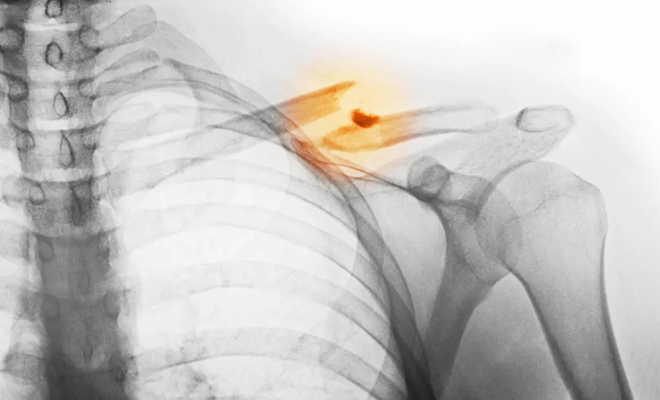

Врачи в Южной Корее начали использовать клей-пистолет, который лечит переломы костей

Клей-пистолет, который обычно ассоциируется с кружками по рукоделию, неожиданно оказался в операционной. Южнокорейские ученые переделали этот простой инструмент так, что он «печатает» кости прямо во время операции. Звучит как безумная идея, но опыты на животных показали: переломы срастаются быстрее и без осложнений.